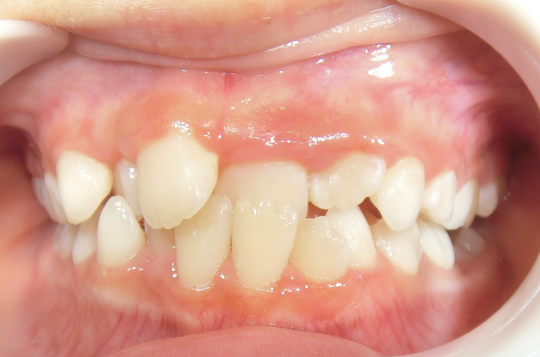

治療前

治療説明

歯科矯正で取り外し可能な矯正方法である床矯正とチンキャップで治療しました

治療期間 4年6か月

治療費用300000 円

治療後

治療の副作用(リスク)歯の動き方には個人差があり、予想された治療期間が延長する可能性があります。。床矯正の使用状況、矯正歯科治療には患者さんの協力が必要であり、それらが治療結果や治療期間に影響します。2次矯正が必要になる場合もあります。